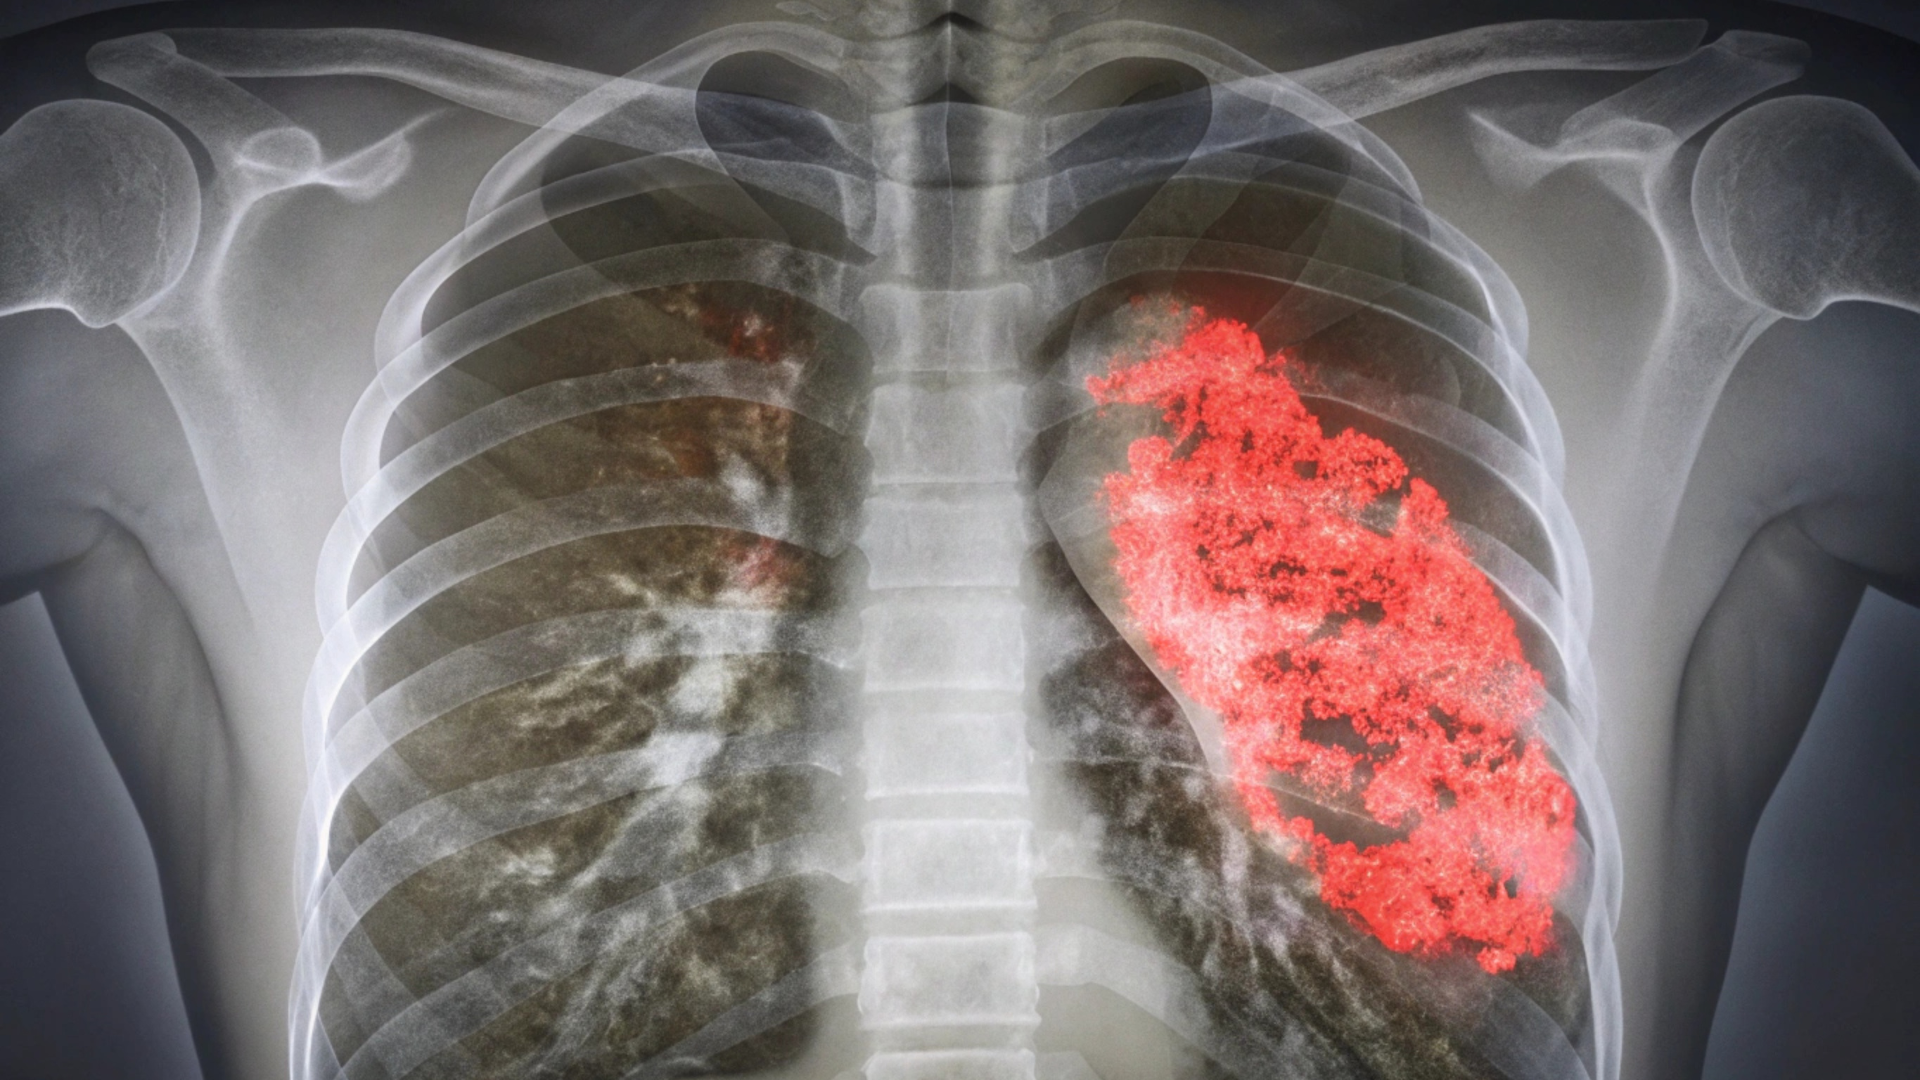

- RSV là nguyên nhân hàng đầu gây viêm phổi ở trẻ sơ sinh và người cao tuổi.

- COVID-19 có thể để lại di chứng hậu COVID kéo dài, ảnh hưởng đến hô hấp và sức khỏe tổng thể.